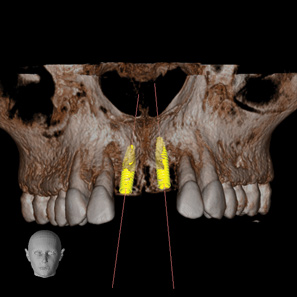

Fig 4. CBCT images: axial (Fig 2) and cross-sectional (Fig 3) views, and 3D reconstruction view (Fig 4) with virtually planned implant Nos. 8 and 9.

Figure 4

Fig 2. CBCT images: axial (Fig 2) and cross-sectional (Fig 3) views, and 3D reconstruction view (Fig 4) with virtually planned implant Nos. 8 and 9.

Figure 2

Fig 3. CBCT images: axial (Fig 2) and cross-sectional (Fig 3) views, and 3D reconstruction view (Fig 4) with virtually planned implant Nos. 8 and 9.

Figure 3

For dental implant-based treatment, the planning phase begins with collection of basic data sets; this is digital touchpoint 1. It includes: (1) a cone-beam CT (CBCT) to view edentulous areas or failing tooth structure, bone, and anatomic landmarks under the soft tissue (Figure 2 through Figure 4); and (2) an intraoral optical scan (IOS) or a scanned model or impression to record the soft tissue and tooth anatomy (Figure 5). The superimposition of the digital imaging and communications in medicine (DICOM) files from the CBCT and the standard tessellation language (STL) files from the IOS allows visualization of how bone, dental structures, and soft tissues relate. Both digital data points are key to implant selection and determining the surrounding bone-grafting needs. An initial treatment plan includes determining the desired implant manufacturer/implant design, size, and positions; these decisions remain the responsibility of the clinician (restoring and surgical team members) and not the technician or planning team.